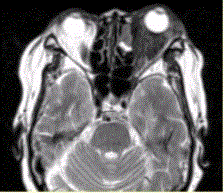

问题 患者女,64岁,左眼突出5年余。查体左眼球前突6mm,眼球运动自如,眼底无异常,下睑扪及边界不清、质软的肿块,视力正常,MR表现如下图。 诊为炎性假瘤,则此例患者的分型应为

选项 A.肿块型 B.弥漫炎症型 C.泪腺型 D.肌炎型 E.眼睑型 F.眼球型

答案 B

解析 B